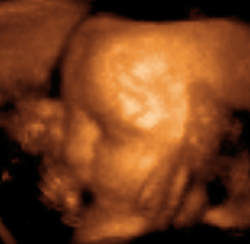

صورة ثلاثية الأبعاد لجنين عمره 29 أسبوع

دخلت الأمواج فوق الصوتية كوسيلة تشخيصية إلى عالم الطب لأول مرة في عام 1942 من قبل العالم Dussik الذي حاول بوساطتها تحديد الأورام الدماغية . وفي عام 1952 استخدم Donald الأمواج فوق الصوتية في بعض القياسات داخل الرحم مثل قياسات رأس الجنين وفحص أعضائه الأخرى وتطور استخدام هذه الأمواج خلال السبعينيات حيث تم استخدام أجهزتها بشكل هائل .

الاستعمالات الخاملة

تتضمن تلك الاستعمالات التي تستخدم فيها الموجات فوق الصوتية في الحصول على المعلومات فقط. على سبيل المثال، يستخدم الأطباء الموجات فوق الصوتية للتأكد من نمو الأجنة0 ويمكن لبعض معدات الموجات فوق الصوتية رسم صورة الجنين على شاشة. كما تساعد هذه المعدات أيضاً في تشخيص الأورام وحصوات المرارة وأمراض القلب، علاوة على بعض الاضطرابات الأخرى. ويعتقد معظم الأطباء أنه لاتوجد آثار جانبية خطيرة للفحوص التي تستخدم فيها الموجات فوق الصوتية.